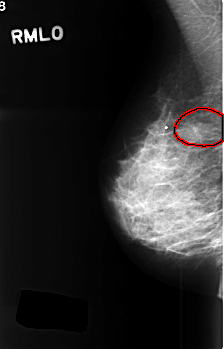

C_0393_1.RIGHT_MLO

RIGHT_MLO LINES 4536 PIXELS_PER_LINE 2904 BITS_PER_PIXEL 12 RESOLUTION 50 OVERLAY

FILE: C_0393_1.RIGHT_MLO.OVERLAY

TOTAL_ABNORMALITIES 1

ABNORMALITY 1

LESION_TYPE MASS SHAPE LOBULATED MARGINS CIRCUMSCRIBED

ASSESSMENT 4

SUBTLETY 4

PATHOLOGY BENIGN

TOTAL_OUTLINES 1

BOUNDARY